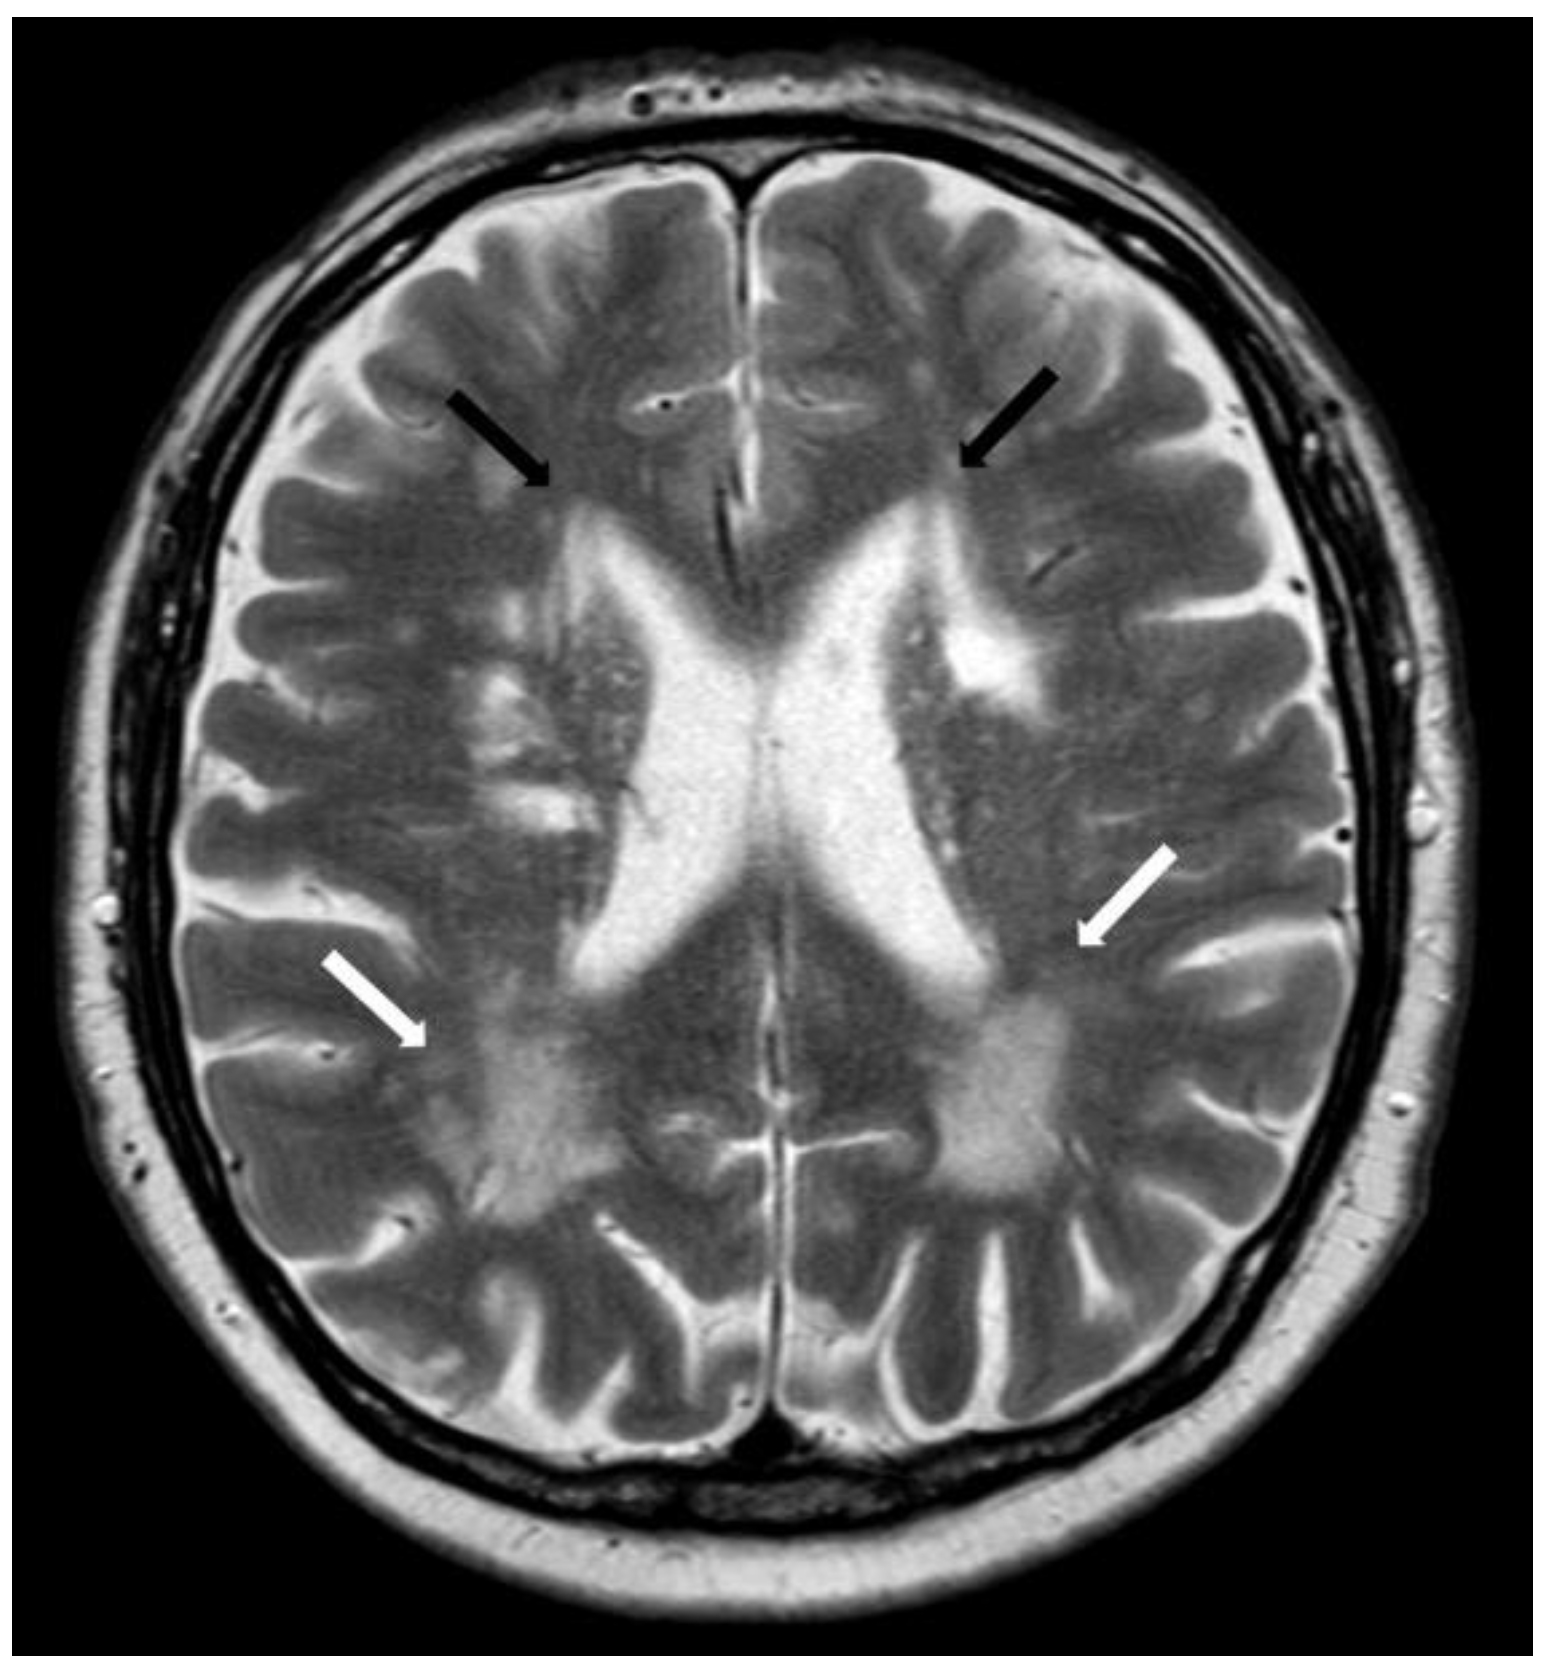

5.1.2. Multiple Cerebral Microbleeds

5.1.3. Convexity Subarachnoid Hemorrhage

5.1.4. Cortical Superficial Siderosis